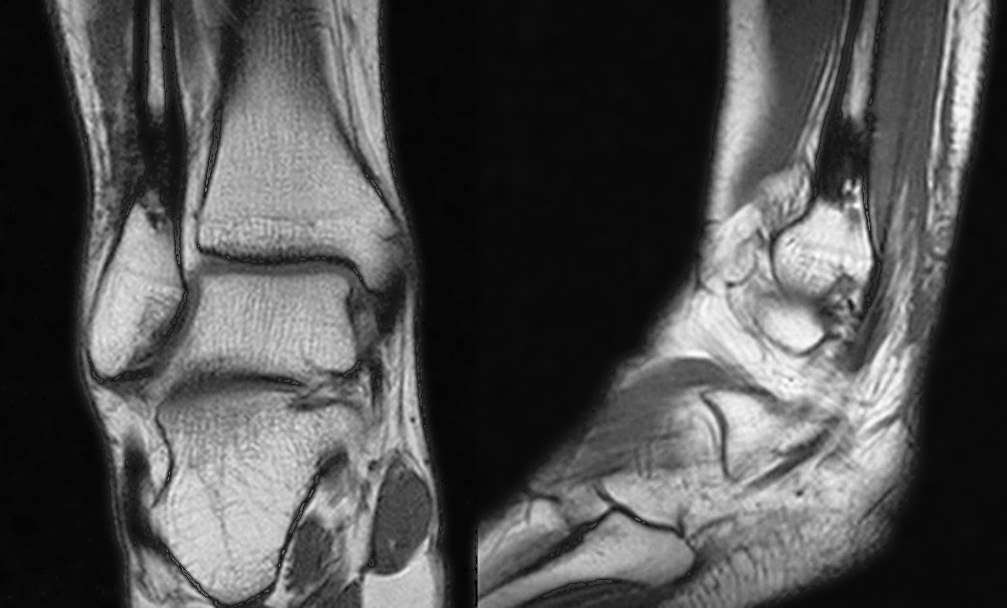

В течение 3 мес. происходила централизация болевого очага в виде усиления болевых ощущений тупого, распирающего характера в области пораженного участка кости (до 6–8 баллов по ВАШ) со значительным усилением в ночное время и при нагрузках. На рентгенограмме наблюдались облитерация костномозговой полости, на магнитно-резонансной томограмме — рубцово-спаечный процесс мягких тканей области нижней трети голени (рис. 3). Отмечались незначительное ограничение амплитуды движений в правом голеностопном суставе, небольшая отечность и температурная асимметрия (местное повышение температуры соответствующего участка кожи).

Рис. 3. Магнитно-резонансная томограмма. Рубцово-спаечный процесс мягких тканей области нижней трети правой голени